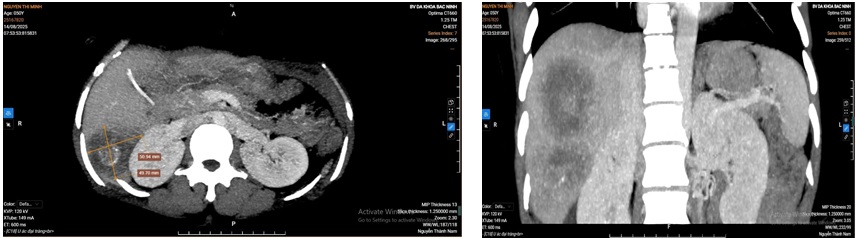

Ngày 11/8/2025, bệnh nhân tái nhập viện tại khoa Ngoại Ung bướu, hình ảnh chụp CLVT bụng và ngực cho thấy bệnh nhân có hai khối u ở gan phải và xuất hiện thêm một khối nhỏ ở gan trái (HPT 3). Đánh giá thể tích gan cho thấy: gan toàn bộ 1390 cm³, gan trái 614 cm³, cân nặng bệnh nhân 43 kg. Sau hội chẩn toàn viện, đã được thống nhất chẩn đoán: Ung thư gan phải ( do ung thư đại tràng di căn gan) kèm khối di căn HPT 3 gan trái/ đã cắt đại tràng phải vét hạch/ đã truyền hoá chất, chức năng gan trong giới hạn bình thường, kết quả đo thể tích gan thấy đáp ứng được phẫu thuật cắt gan phải. Bệnh nhân đã được chỉ định cắt gan phải, lấy nhân di căn HPT 3 gan trái.

Ảnh: Hình ảnh CLVT gan, nhiều khối tổn thương gan phải, gan trái còn bảo tồn.